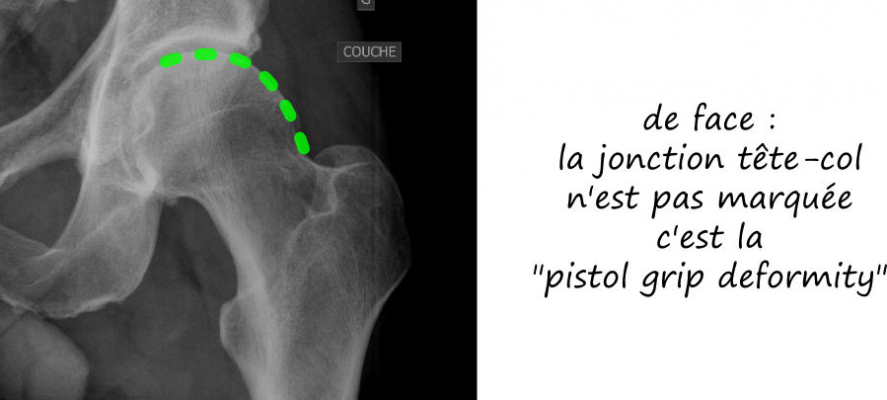

Radiologie standard

Le conflit fémoro acétabulaire se décèle sur de simples radiographies de la hanche, notemment sur le profil de DUNN qui expose la face antérieure du col fémoral. Sur cette radio est estimée l’angle alpha, correpondant à l’angle formé par l’axe du col fémoral et une droite passsant par le centre de la tete fémorale et le point de décrochage de la jonction tete-col, et qui est normalement de l’ordre de 45°; il est augmenté dans les conflits par effet came, comme sur cette radio ci dessous.